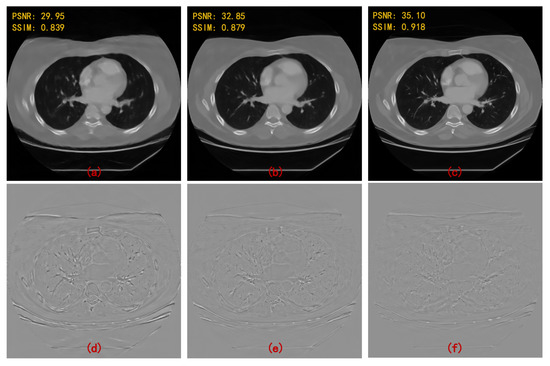

| 90 Views | 60 Views | |||

|---|---|---|---|---|

| PSNR | SSIM | PSNR | SSIM | |

| FBPConvNet [13] | 37.611 | 0.921 | 35.578 | 0.896 |

| RED-CNN [14] | 37.209 | 0.902 | 34.528 | 0.859 |

| DD-Net [22] | 36.380 | 0.912 | 34.424 | 0.892 |

| MWCNN [23] | 38.664 | 0.943 | 36.531 | 0.921 |

| HDNet (WCNN-based) [29] | 34.506 | 0.900 | 32.259 | 0.869 |

| HDNet (Unet-based) [30] | 35.459 | 0.903 | 33.377 | 0.886 |

| HDNet (WUnet-based) | 36.750 | 0.924 | 35.132 | 0.904 |

| HDNet (MWCNN-based) | 40.204 | 0.956 | 37.718 | 0.938 |